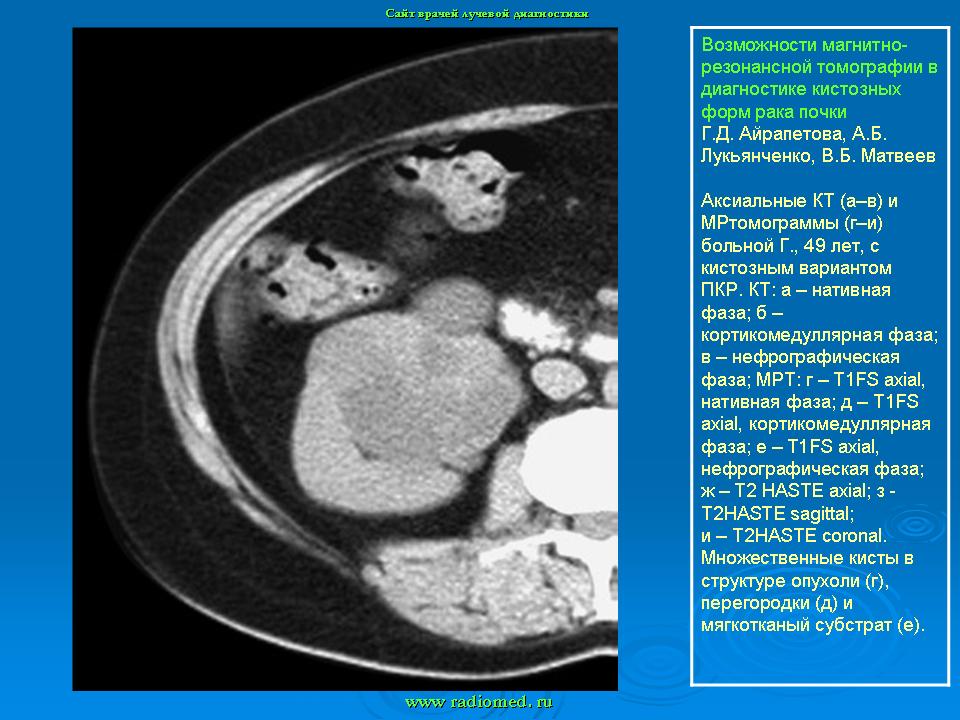

МРТ. Почки и мочевыводящие пути.